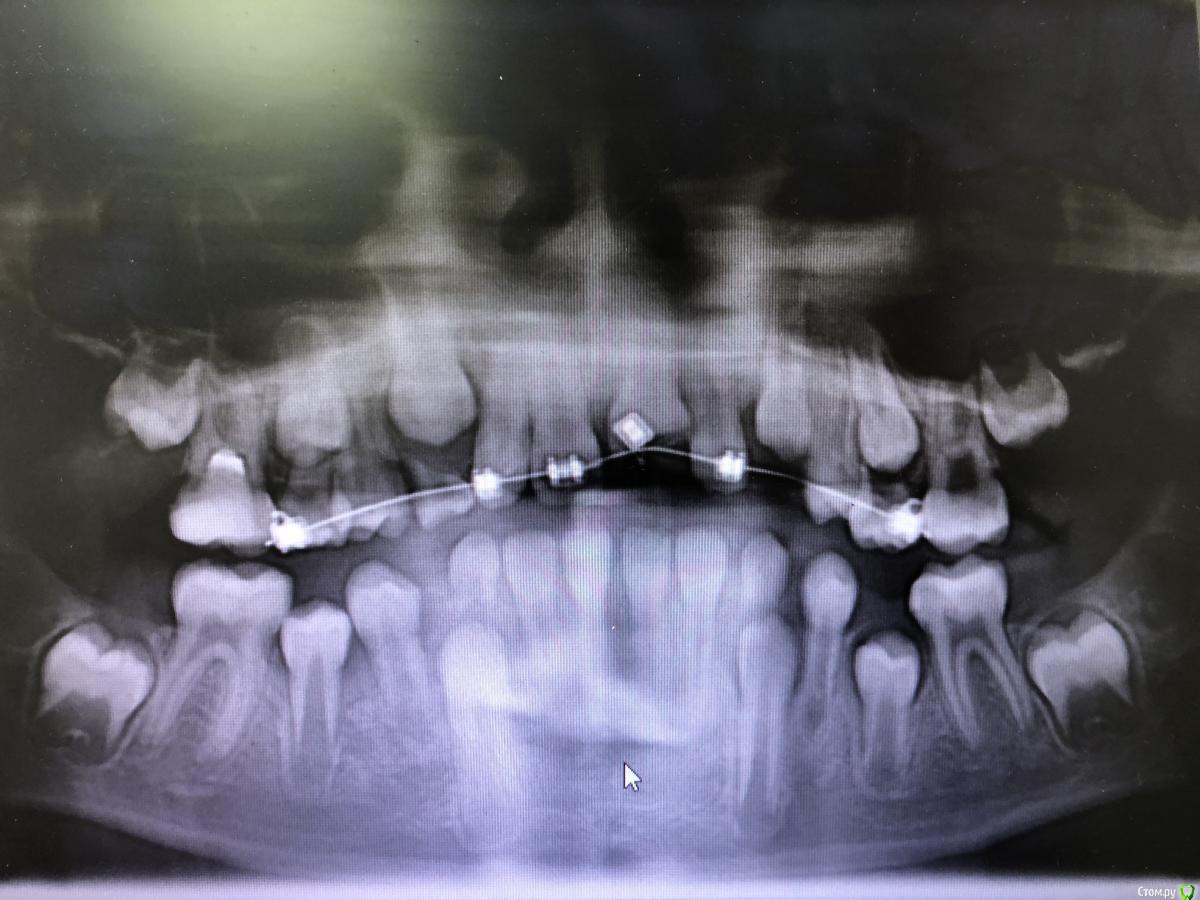

dashkovski Опубликовано 24 августа, 2018 Поделиться Опубликовано 24 августа, 2018 (изменено) Дорогие коллеги! Подскажите что делать. Пришёл мальчик 10 лет, 4 июля произошёл перелом и вколоченный вывих 21 зуба. Они обратились в одну из клиник нашего города, там им сделали ОПГ и почему то реплантацию сразу не провели, а поставили частичную брекет систему и приклеили кнопку на вколоченный зуб, при этом дугу поставили очень слабую 014NiTi . Спустя месяц они пришли ко мне на приём, решив что в той клинике им ни чем не помогли. Я поменяла дугу на более жесткую 16\22 NiTi, но спустя 3 недели никаких изменений не произошло, разве что соседние зубы начали подниматься, по снимку передний отдел виден не четко, но все же. И похоже на развивающийся периодонтит. Есть ли смысл сейчас реплантировать зуб и депульпировать и протезировать? Хотелось бы его сохранить до 18 лет Изменено 24 августа, 2018 пользователем dashkovski Ссылка на комментарий

red_butler Опубликовано 25 августа, 2018 Поделиться Опубликовано 25 августа, 2018 Коллеги, я смотрел этого пациента. Зуб вколочен полностью, слизистая спокойная, отделяемого нет, на рвг перелом коронарной части на 1/2, эод провести не возможно. Снимок смогу прикрепить в понедельник 2 Ссылка на комментарий